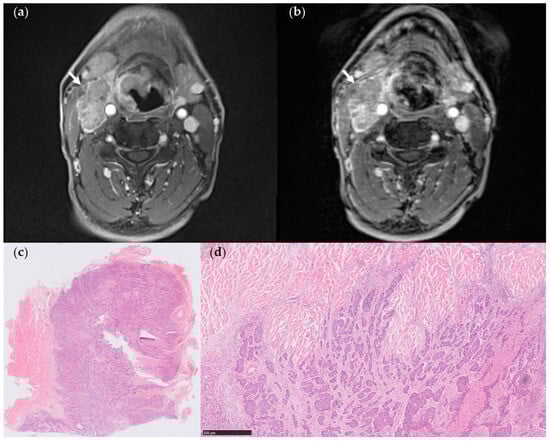

3.2. Comparison between StarVIBE and VIBE

3.3. Association of MR Features with Histologically Confirmed ENE